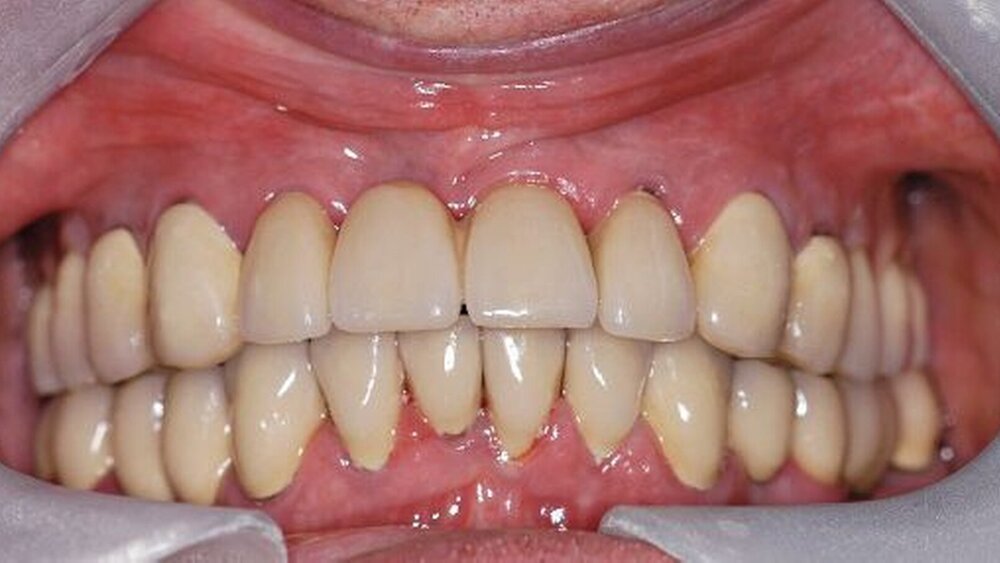

In der darauf folgenden Sitzung wurden alle Kronen und Brücken sowie die teleskopgetragene, partielle obere Prothese für einen Zeitraum von sieben Tagen zum Probetragen mittels eines Zements auf Zinkoxid-Eugenol-Basis eingegliedert. Dem Patienten sollte durch das Probetragen der Restaurationen beziehungsweise des angefertigten Zahnersatzes die Möglichkeit gegeben werden, sowohl die Funktion beim Essen und Sprechen als auch die Ästhetik im sozialen Umfeld zu testen. Ein erneutes Entnehmen der Restaurationen wäre – für den Fall notwendiger Korrekturen – somit ohne Weiteres möglich gewesen. Da der Patient sowohl die Funktion als auch die Ästhetik betreffend keine Änderungswünsche vorbrachte und auch keine neuerlichen Beschwerden aufgetreten waren, konnten die Restaurationen nach besagtem Tragezeitraum von sieben Tagen entnommen, gesäubert und mittels eines Glasionomerzements definitiv befestigt werden. Im Anschluss wurden erneut Situationsabformungen der Kiefer genommen und der Patient erhielt nach erneutem Checkbiss-Registrat, eine okklusal adjustierte Stabilisierungsschiene im Unterkiefer. Diese dient der Therapie der beschriebenen Bruxismusproblematik und gewährleistet einen langfristen Erfolg der eingegliederten prothetischen Restaurationen (Abbildungen 13a, 13b, 13c, 14, 15a, 15b, 15c).

Abschließend kann somit festgehalten werden, dass durch die gewählte Restaurationsform sowie durch die Art der technischen Umsetzung ein funktionell und ästhetisch sehr gutes Ergebnis erreicht werden konnte. Die Prognose des angefertigten Zahnersatzes ist bei entsprechender Compliance des Patienten sowie aufgrund der guten werkstofftechnischen Eigenschaften über einen Zeitraum von vielen Jahren als sehr gut einzustufen (Abbildungen 16a, 16b, 16c, 16d, 16e ).